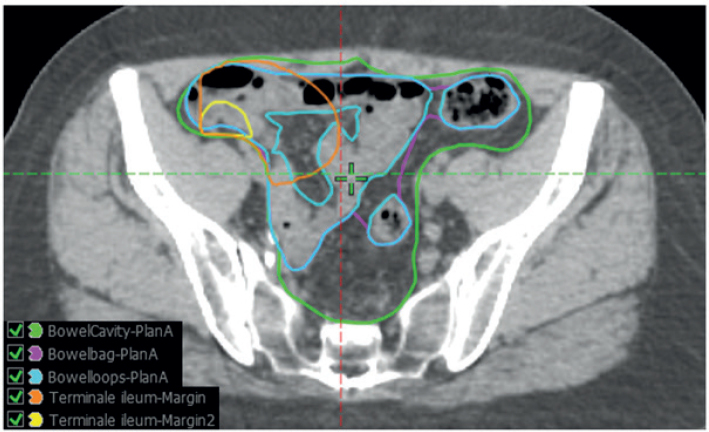

Background and purpose: Treatment-related diarrhea is a challenge for patients treated with chemo-radiotherapy (CRT) for anal cancer in a curative setting. This study aims to investigate dosimetric and clinical predictors of acute and late diarrhea for patients treated with CRT or radiotherapy (RT) alone for anal cancer. Additionally, to investigate different bowel contouring methods ability to predict diarrhea. Patient/material and methods: Patients treated with CRT or RT alone in the prospective, observational DACG-I Plan-A study (2015-2021) were included. Toxicity endpoints were acute grade ≥2 diarrhea, and late grade ≥1 diarrhea recorded at 1 year after treatment (Common Terminology Criteria of Adverse Events (CTCAE), v4.0). Bowel volumes were contoured on the planning computed tomography (CT) as bowel cavity, bowel bag, individual bowel loops, and terminal ileum. Dosimetric variables included V15Gy, V30Gy, and V45Gy for the different bowel volumes. Clinical variables included tumor size, N-stage, and chemotherapy regimen. Logistic regression was used to evaluate the association between variables and toxicity.